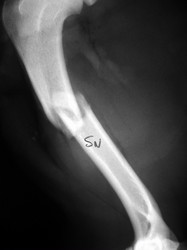

Fijación Externa

Fijación externa en IVOT

PRÁCTICAS CURSO DE FIJACIÓN EXTERNA PERFECCIONAMIENTO.

Húmero.